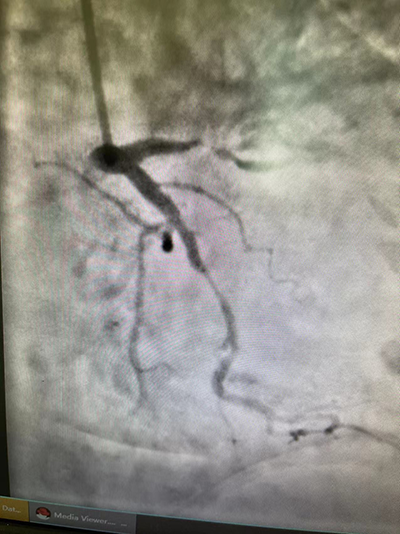

术后造影:前降支植入两枚支架(红色箭头)血管恢复正常

术后患者胸痛症状得到明显缓解,但血压仍较低,在CCU病房全程监护及心内一科医护团队的精心治疗与护理下,现患者已经转危为安,病情非常平稳。正是因为得到了这样及时、规范的救治,才为患者赢得了生的希望。家属满怀感激的说:“感谢刁青主任、王虹副主任及心内科的全体医护人员,是你们给了我母亲第二次生命”。